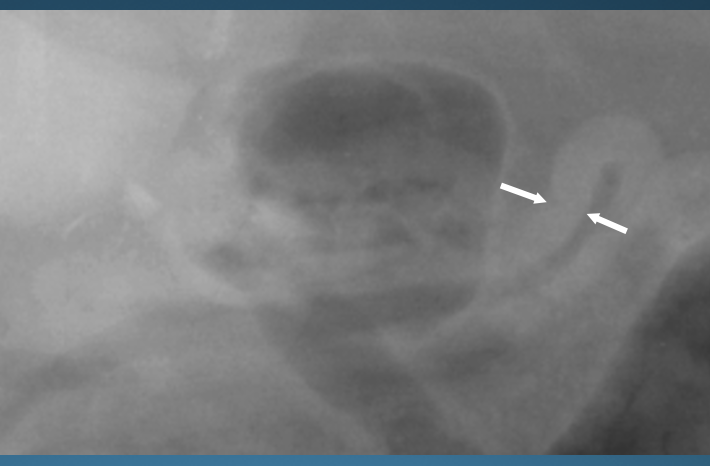

What is shown in these images?

A

normal feline stomach